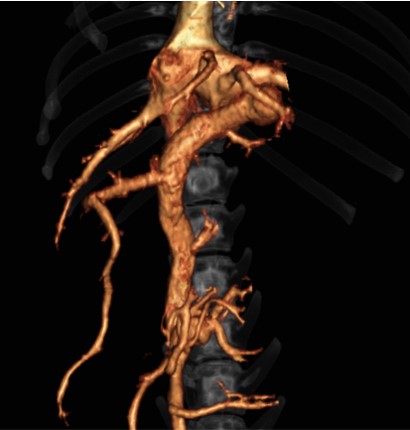

대표질환

- 종양 진단 (두경부, 흉강, 복강, 사지 골격) 및 전이 평가

- 골격계 질환 및 골절 합병증 평가

- 혈관 기형 (PDA, PSS, vascular ring anomaly 등)

- 척추 질환 (척추 골절, hemivertebra)

- 폐 질환

전신문맥단락(PSS)